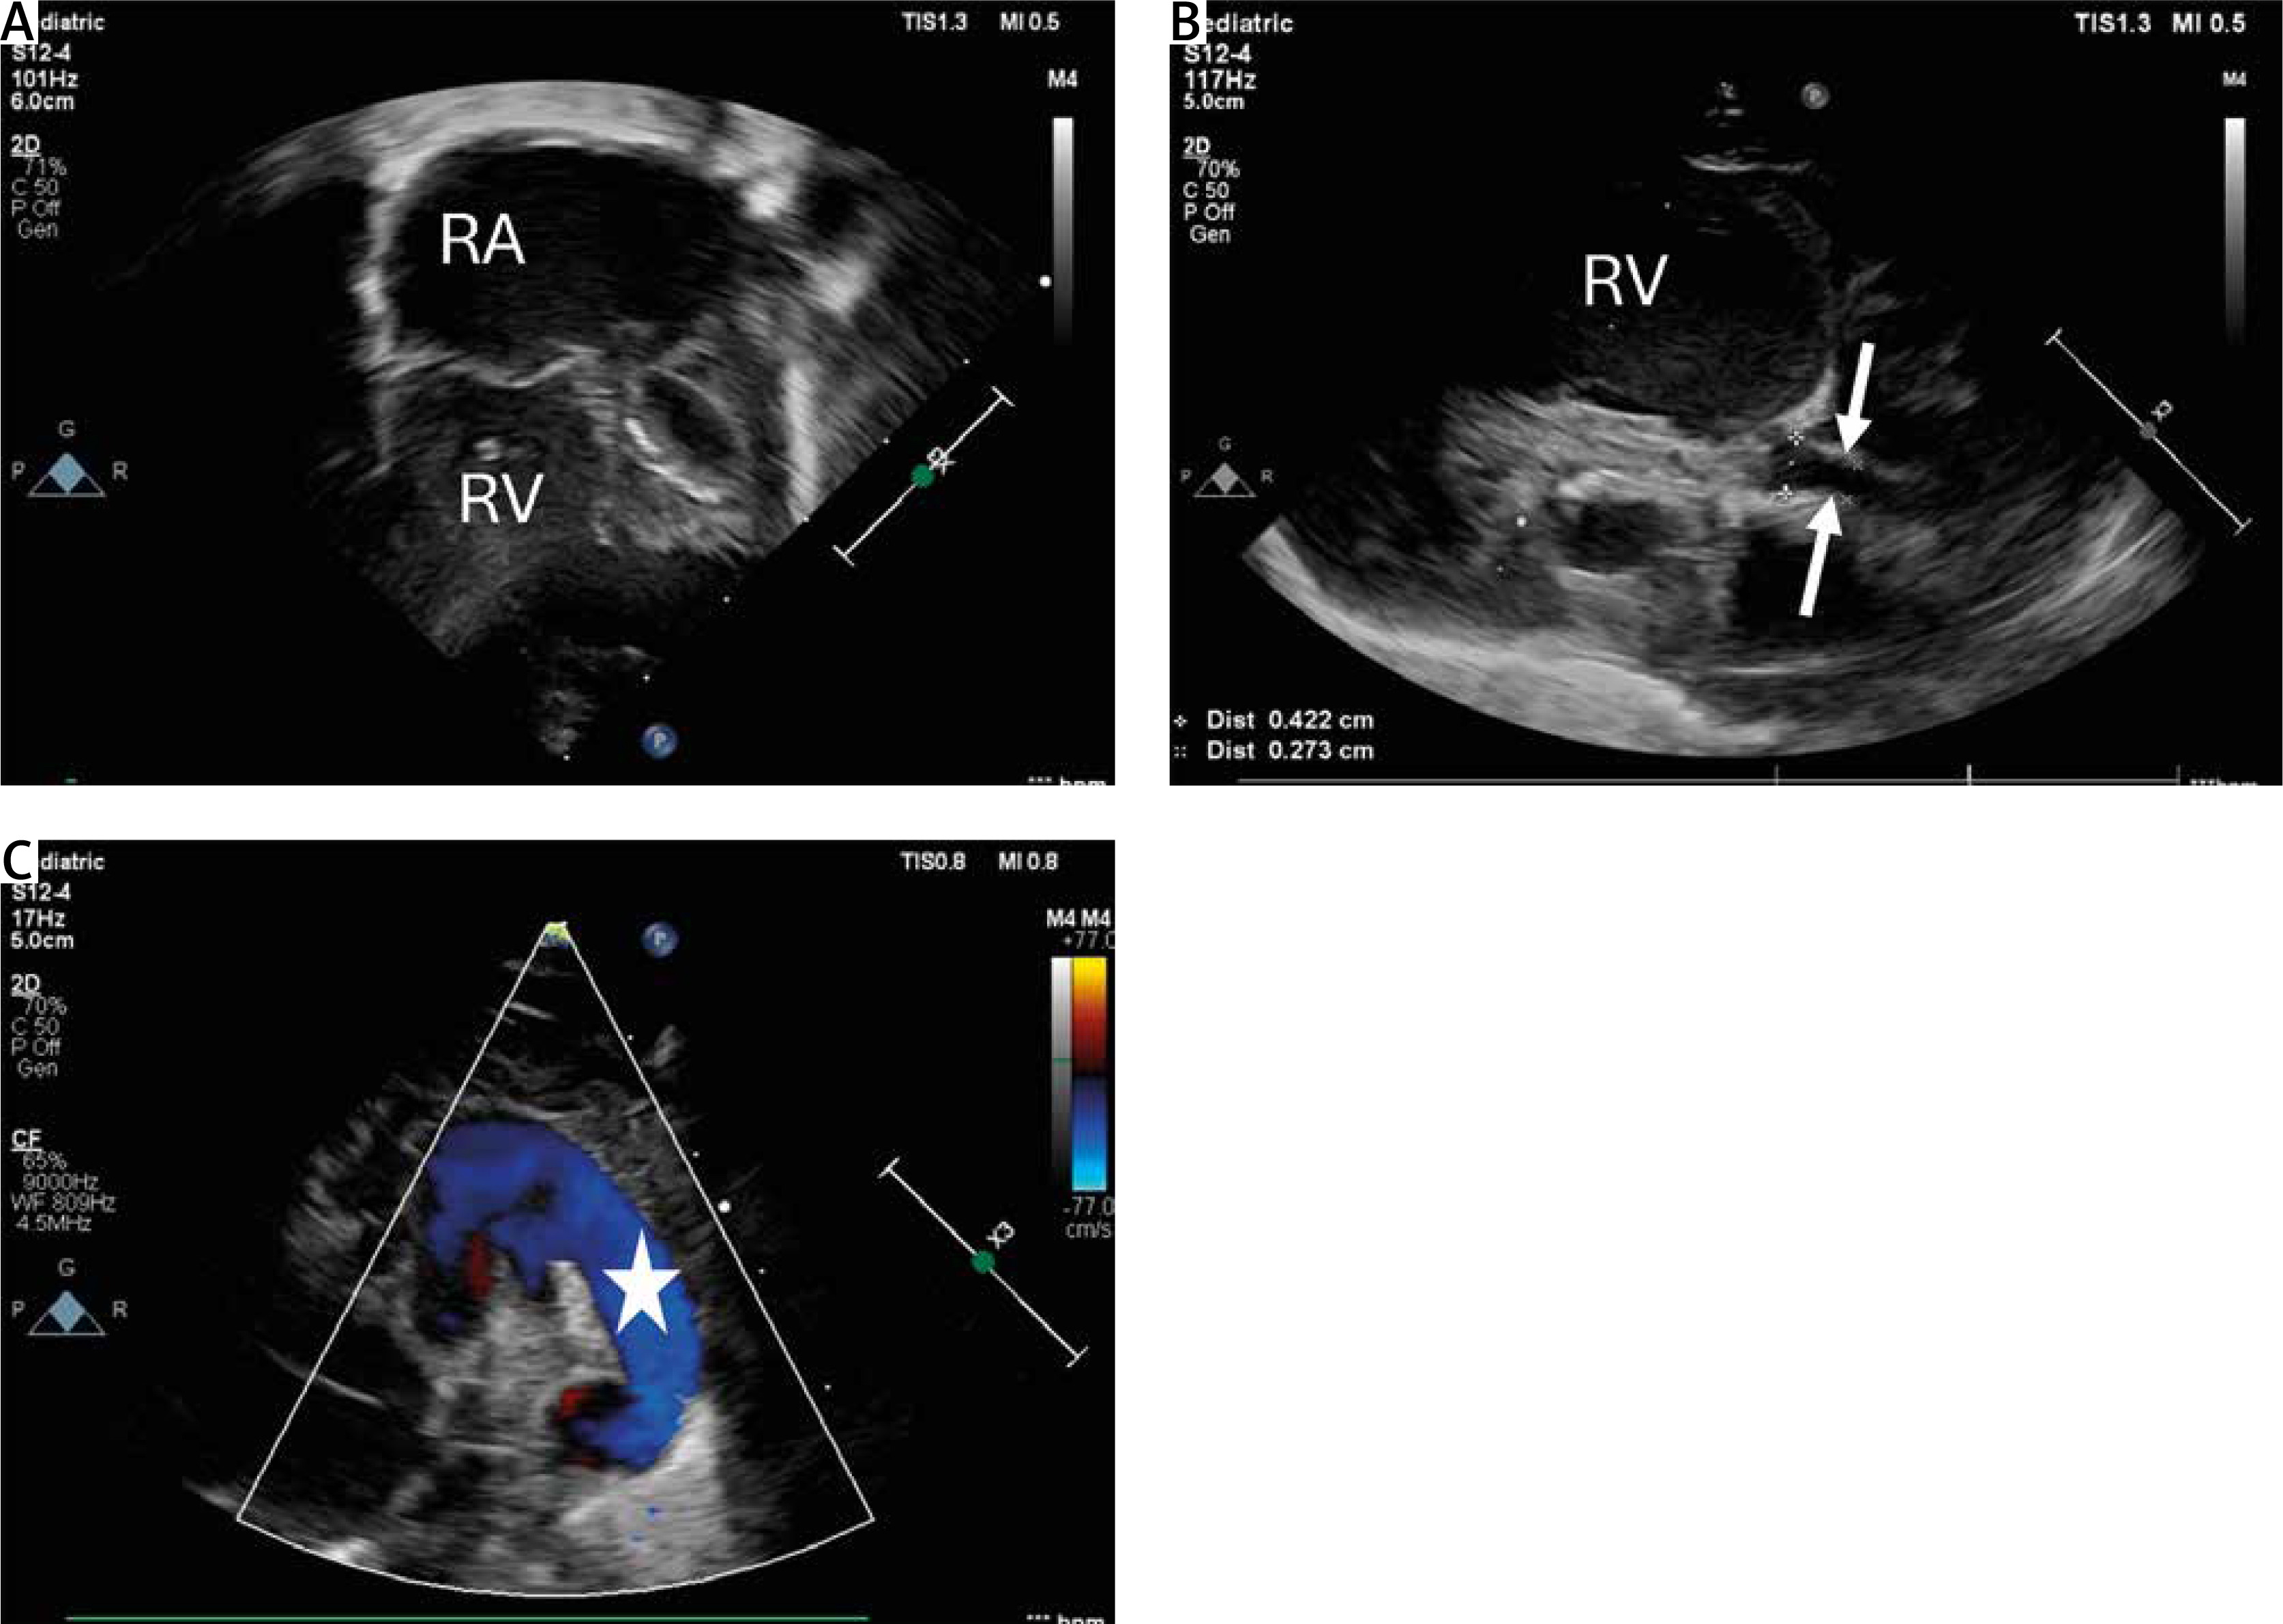

Figure 1

Transthoracic echocardiography (TTE) showing hypoplastic left heart syndrome. A – TTE. 2DE. Apical 4 chamber view showing dilated right atrium and right ventricle and extremely hypoplastic left ventricle with fibroelastosis. B – Parasternal longitudinal axis. Aortic valve atresia with extremely hypoplastic ascending aorta (2.7 mm) (white arrows) and bulbus of the aorta (4.2 mm). C – Parasternal short axis view with color Doppler flow showing wide patent arterial duct (white star) with right-to-left shunting

RA – right atrium, RV – right ventricle.